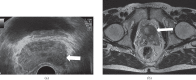

Transrectal ultrasound (TRUS) was first developed in the 1970s. TRUS-guided biopsy, under local anaesthetic and prophylactic antibiotics, is now the most widely accepted method to diagnose prostate cancer. However, the sensitivity and specificity of greyscale TRUS in the detection of prostate cancer is low. Prostate cancer most commonly appears as a hypoechoic focal lesion in the peripheral zone on TRUS but the appearances are variable with considerable overlap with benign lesions. Because of the low accuracy of greyscale TRUS, TRUS-guided biopsies have become established in the acquisition of systematic biopsies from standard locations. The number of systematic biopsies has increased over the years, with 10-12 cores currently accepted as the minimum standard. This article describes the technique of TRUS and biopsy and its complications. Novel modalities including contrast-enhanced modes and elastography as well as fusion techniques for increasing the sensitivity of TRUS-guided prostate-targeted biopsies are discussed along with their role in the diagnosis and management of prostate cancer.